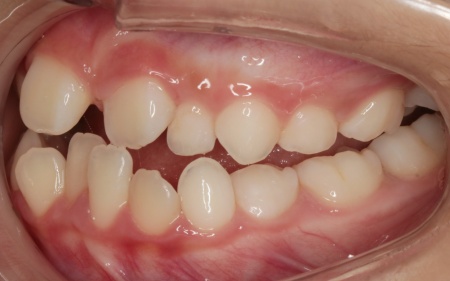

10歳女の子 顎の幅を広げる装置とマウスピース型の矯正装置で反対咬合を改善した症例

拝見したところ、上前歯が下前歯の内側に入り込む「反対咬合(こうごう)」が認められました。

詳しい検査の結果、患者様の反対咬合は歯の位置の問題ではなく、上顎の発育が十分ではないことが主な原因と考えられます。

このまま放置すると、顎のずれが大きくなり、将来的に外科手術が必要になるリスクがあるだけでなく、歯の位置関係が乱れることで発音に影響が出るおそれもあります。

また、お子様の場合は成長期のうちに顎の発育を適切に促すことが重要なので、早期に矯正治療を開始する必要があると診断しました。

まずは、「バイオブロック」による治療で上顎の発育を促すこと、その後、前歯の位置を細かく整えるためマウスピース型矯正装置「インビザラインファースト」と、上顎を前方へ引き出す「前方牽引装置」を併用する治療計画を提案しました。